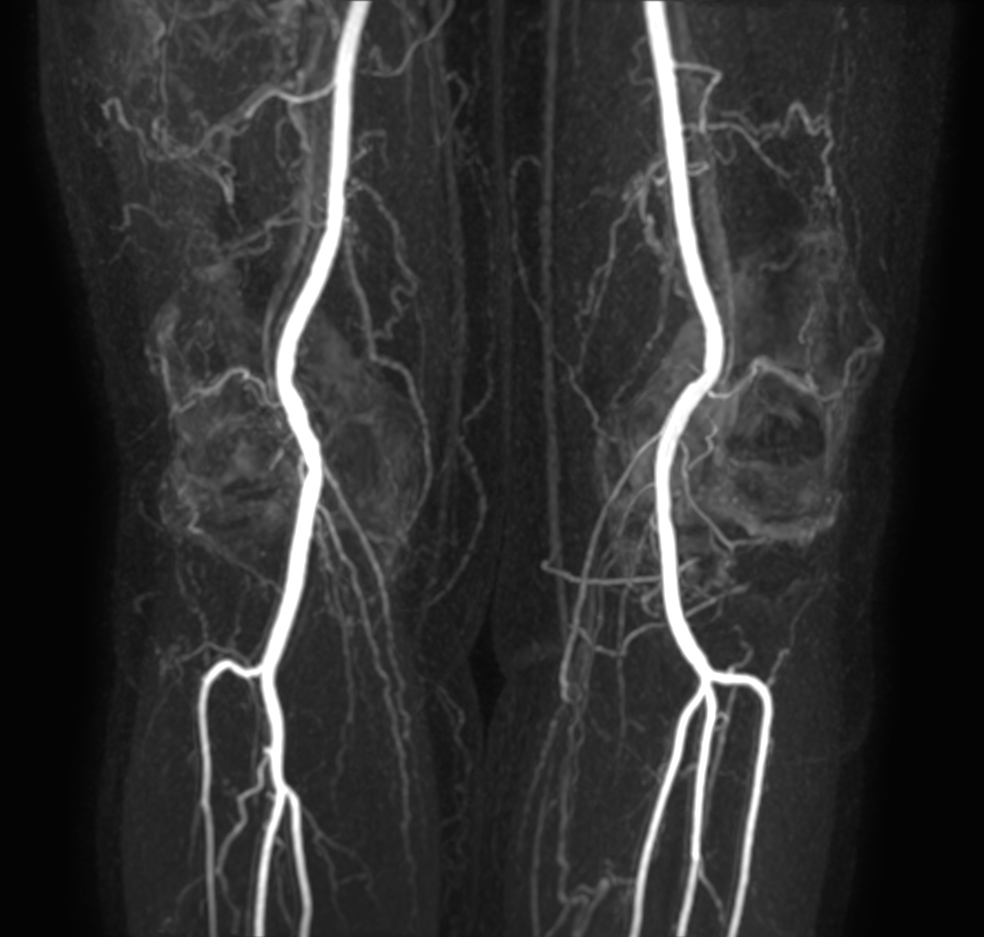

Patient with a known stent in the abdominal veins. Subtraction-less mDIXON MRA run-off is performed using a combination of Compressed SENSE and enhanced gradient strength to increase both in-plane and through-plane spatial resolution. The station covering the feet has been rescanned with a Compressed SENSE factor of 14, resulting in a time resolved scan with a dynamic time of only 4 seconds.

mDIXON MRA (MIP) - Upper leg